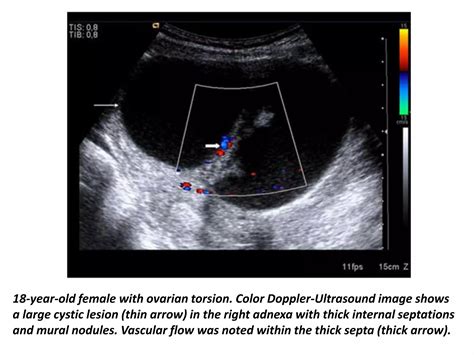

Several factors increase the risk of developing this condition, most notably the presence of an ovarian cyst or a benign mass, such as a dermoid cyst, which makes the ovary heavy and prone to twisting. During a physical examination, the physician will assess for tenderness, but because the symptoms can be vague, imaging is required to confirm the diagnosis and rule out other potential causes, such as ectopic pregnancy or pelvic inflammatory disease.

Peripheral Displacement of Follicles

In a healthy ovary, follicles are typically distributed throughout the ovarian tissue. When the ovary is enlarged due to edema caused by torsion, the follicles are often pushed to the periphery of the ovary, creating a “string of pearls” appearance. This is a classic sign often noted by ultrasound technicians and radiologists.

Abnormal Blood Flow Patterns

While the absence of flow is the most definitive sign, it is also a late finding. Radiologists look for subtle changes, such as high-resistance flow in the ovarian artery, which suggests the ovary is struggling to receive blood against the pressure of the twist. The presence of a “whirlpool sign”—a twisting of the vascular pedicle—is highly specific for torsion, though it can be technically difficult to visualize.